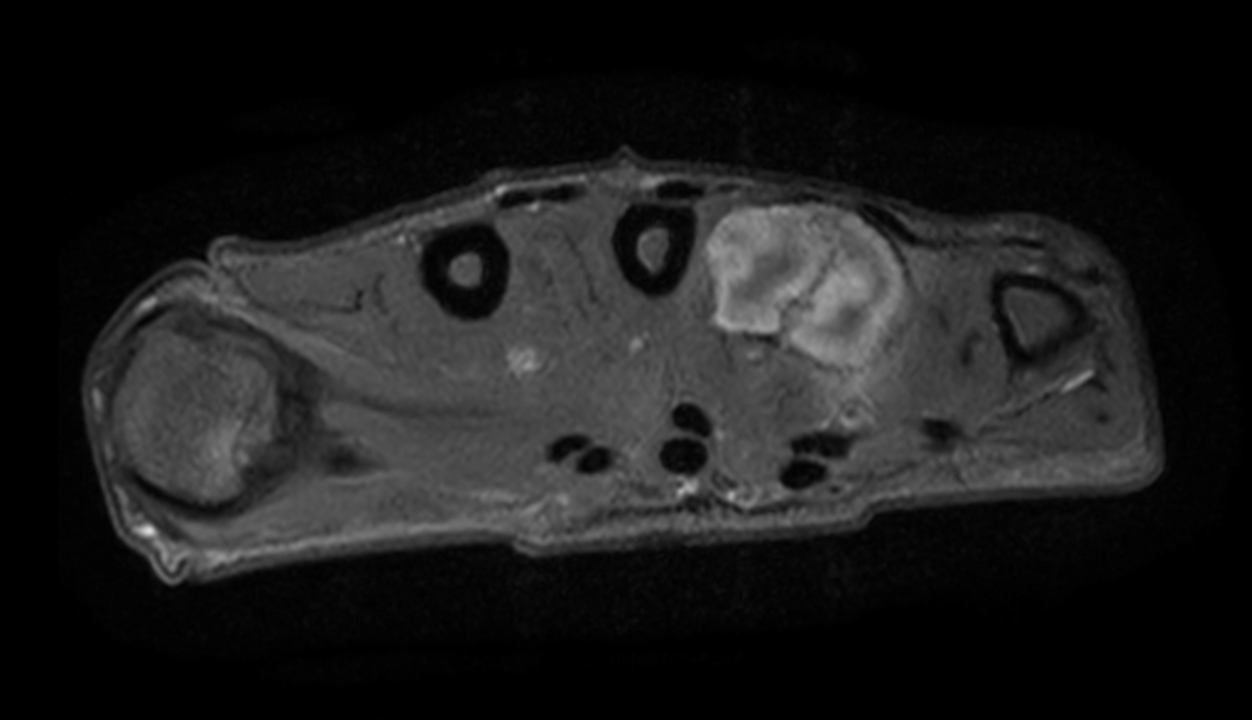

Axial PDw mDIXON XD TSE (Water only)

Axial PDw mDIXON XD TSE (In Phase)

Axial PDw mDIXON XD TSE (Partial FatSat)